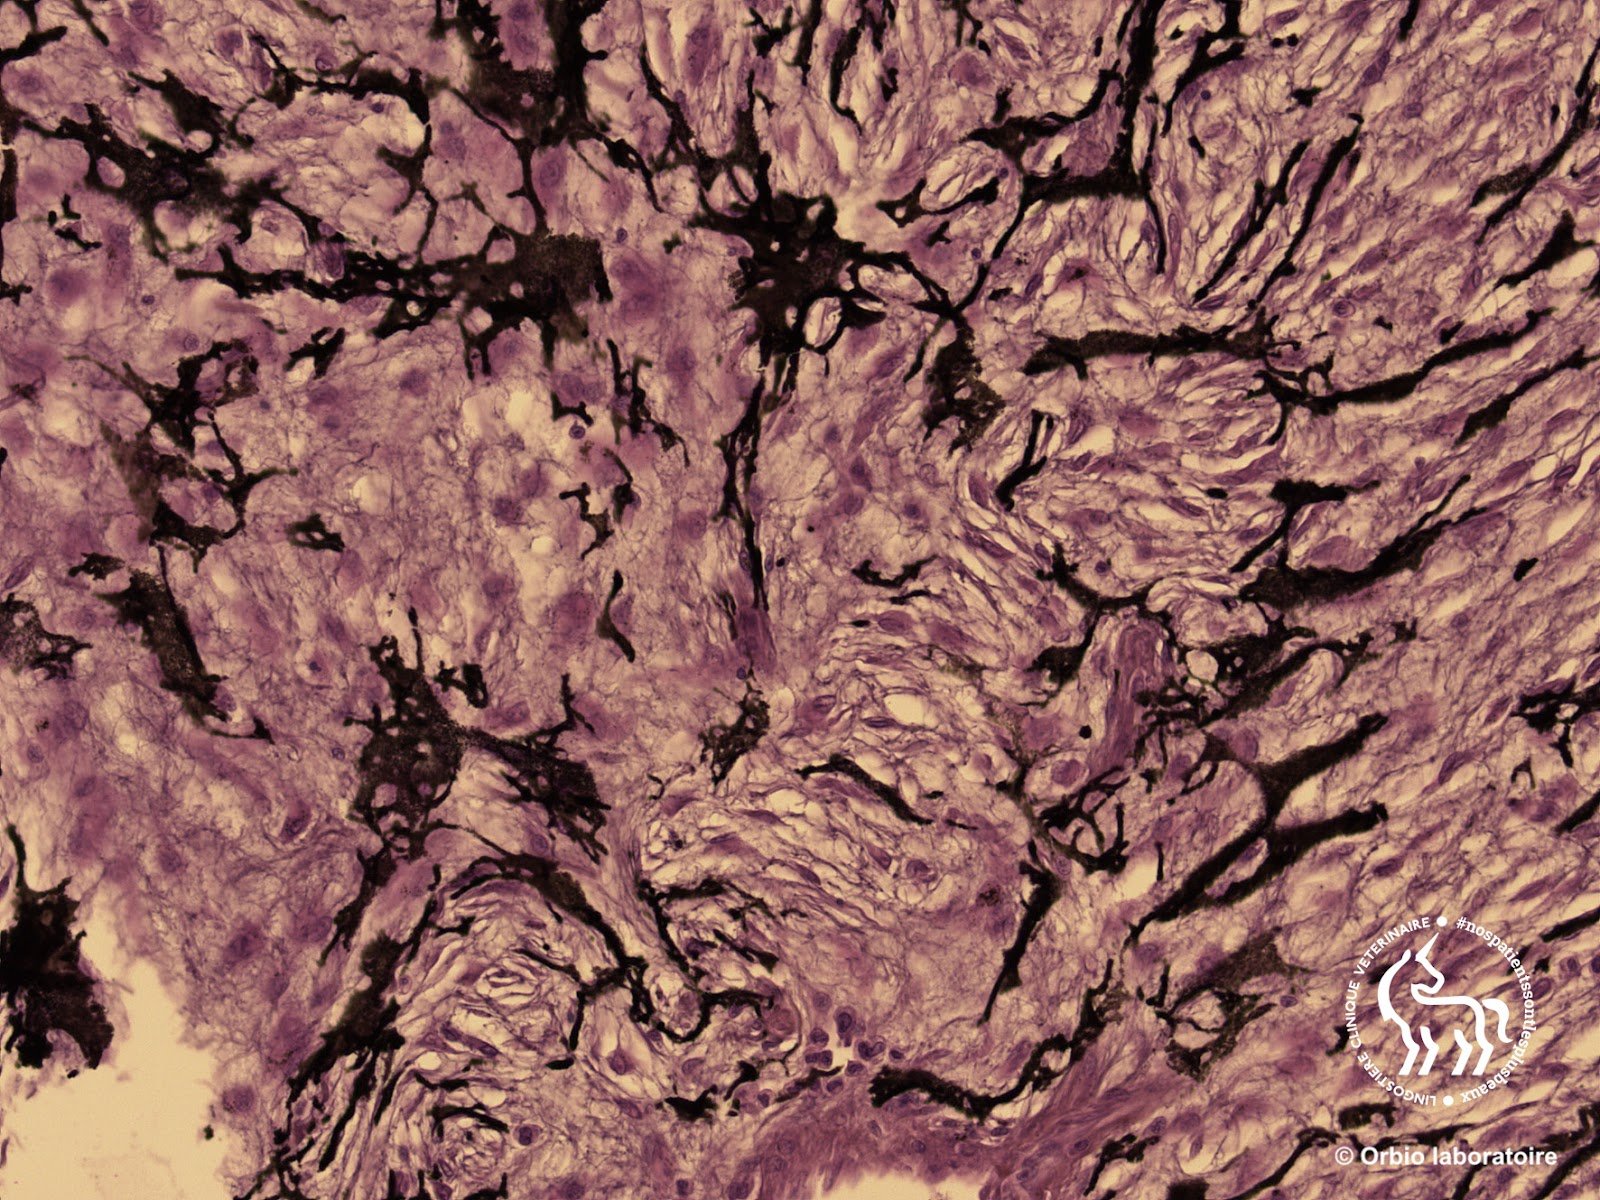

Analyse Histopathologique

Le diagnostic de certitude repose exclusivement sur l’examen microscopique des tissus prélevés.